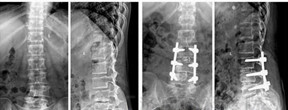

1月19日,44岁腰椎滑脱合并席汉氏综合症患者尹某,在南通中山骨科医院成功完成腰椎滑脱植骨融合内固定术。这是我院接收的首例罕见席汉氏综合症患者,而本次手术的成功也意味着本地合并席汉氏综合症的骨病患者将不必前往外省进行相关的手术治疗。<<骨科医生在线解答病情

自尹某入院以来,我院做了充分的术前准备。专家多次会诊讨论治疗方案,调节患者激素水平。在与患者家属进行充分沟通并获得理解的基础上,为其确定了手术方案。待尹某激素水平达到预期峰值,身体各项机能指标稳定,1月19日上午,我院脊柱科主任以及麻醉科各位同仁协同合作,严密监测,为患者实施腰椎内路椎体复位椎管减压植骨融合内固定术,手术非常顺利。

术后随访,患者全身体质恢复良好,疗效满意。席汉氏综合症病例在临床上已越来越少,此病例的成功救治不仅体现了南通中山骨科医院在实施腰椎滑脱植骨融合内固定术合并全身系统性危重疾病治疗中的实力,更体现了南通中山骨科医院科室间团结合作、以高度的责任感履行医者神圣的职责。<<手术可以申请医保吗?报销比例是多少?点击在线咨询